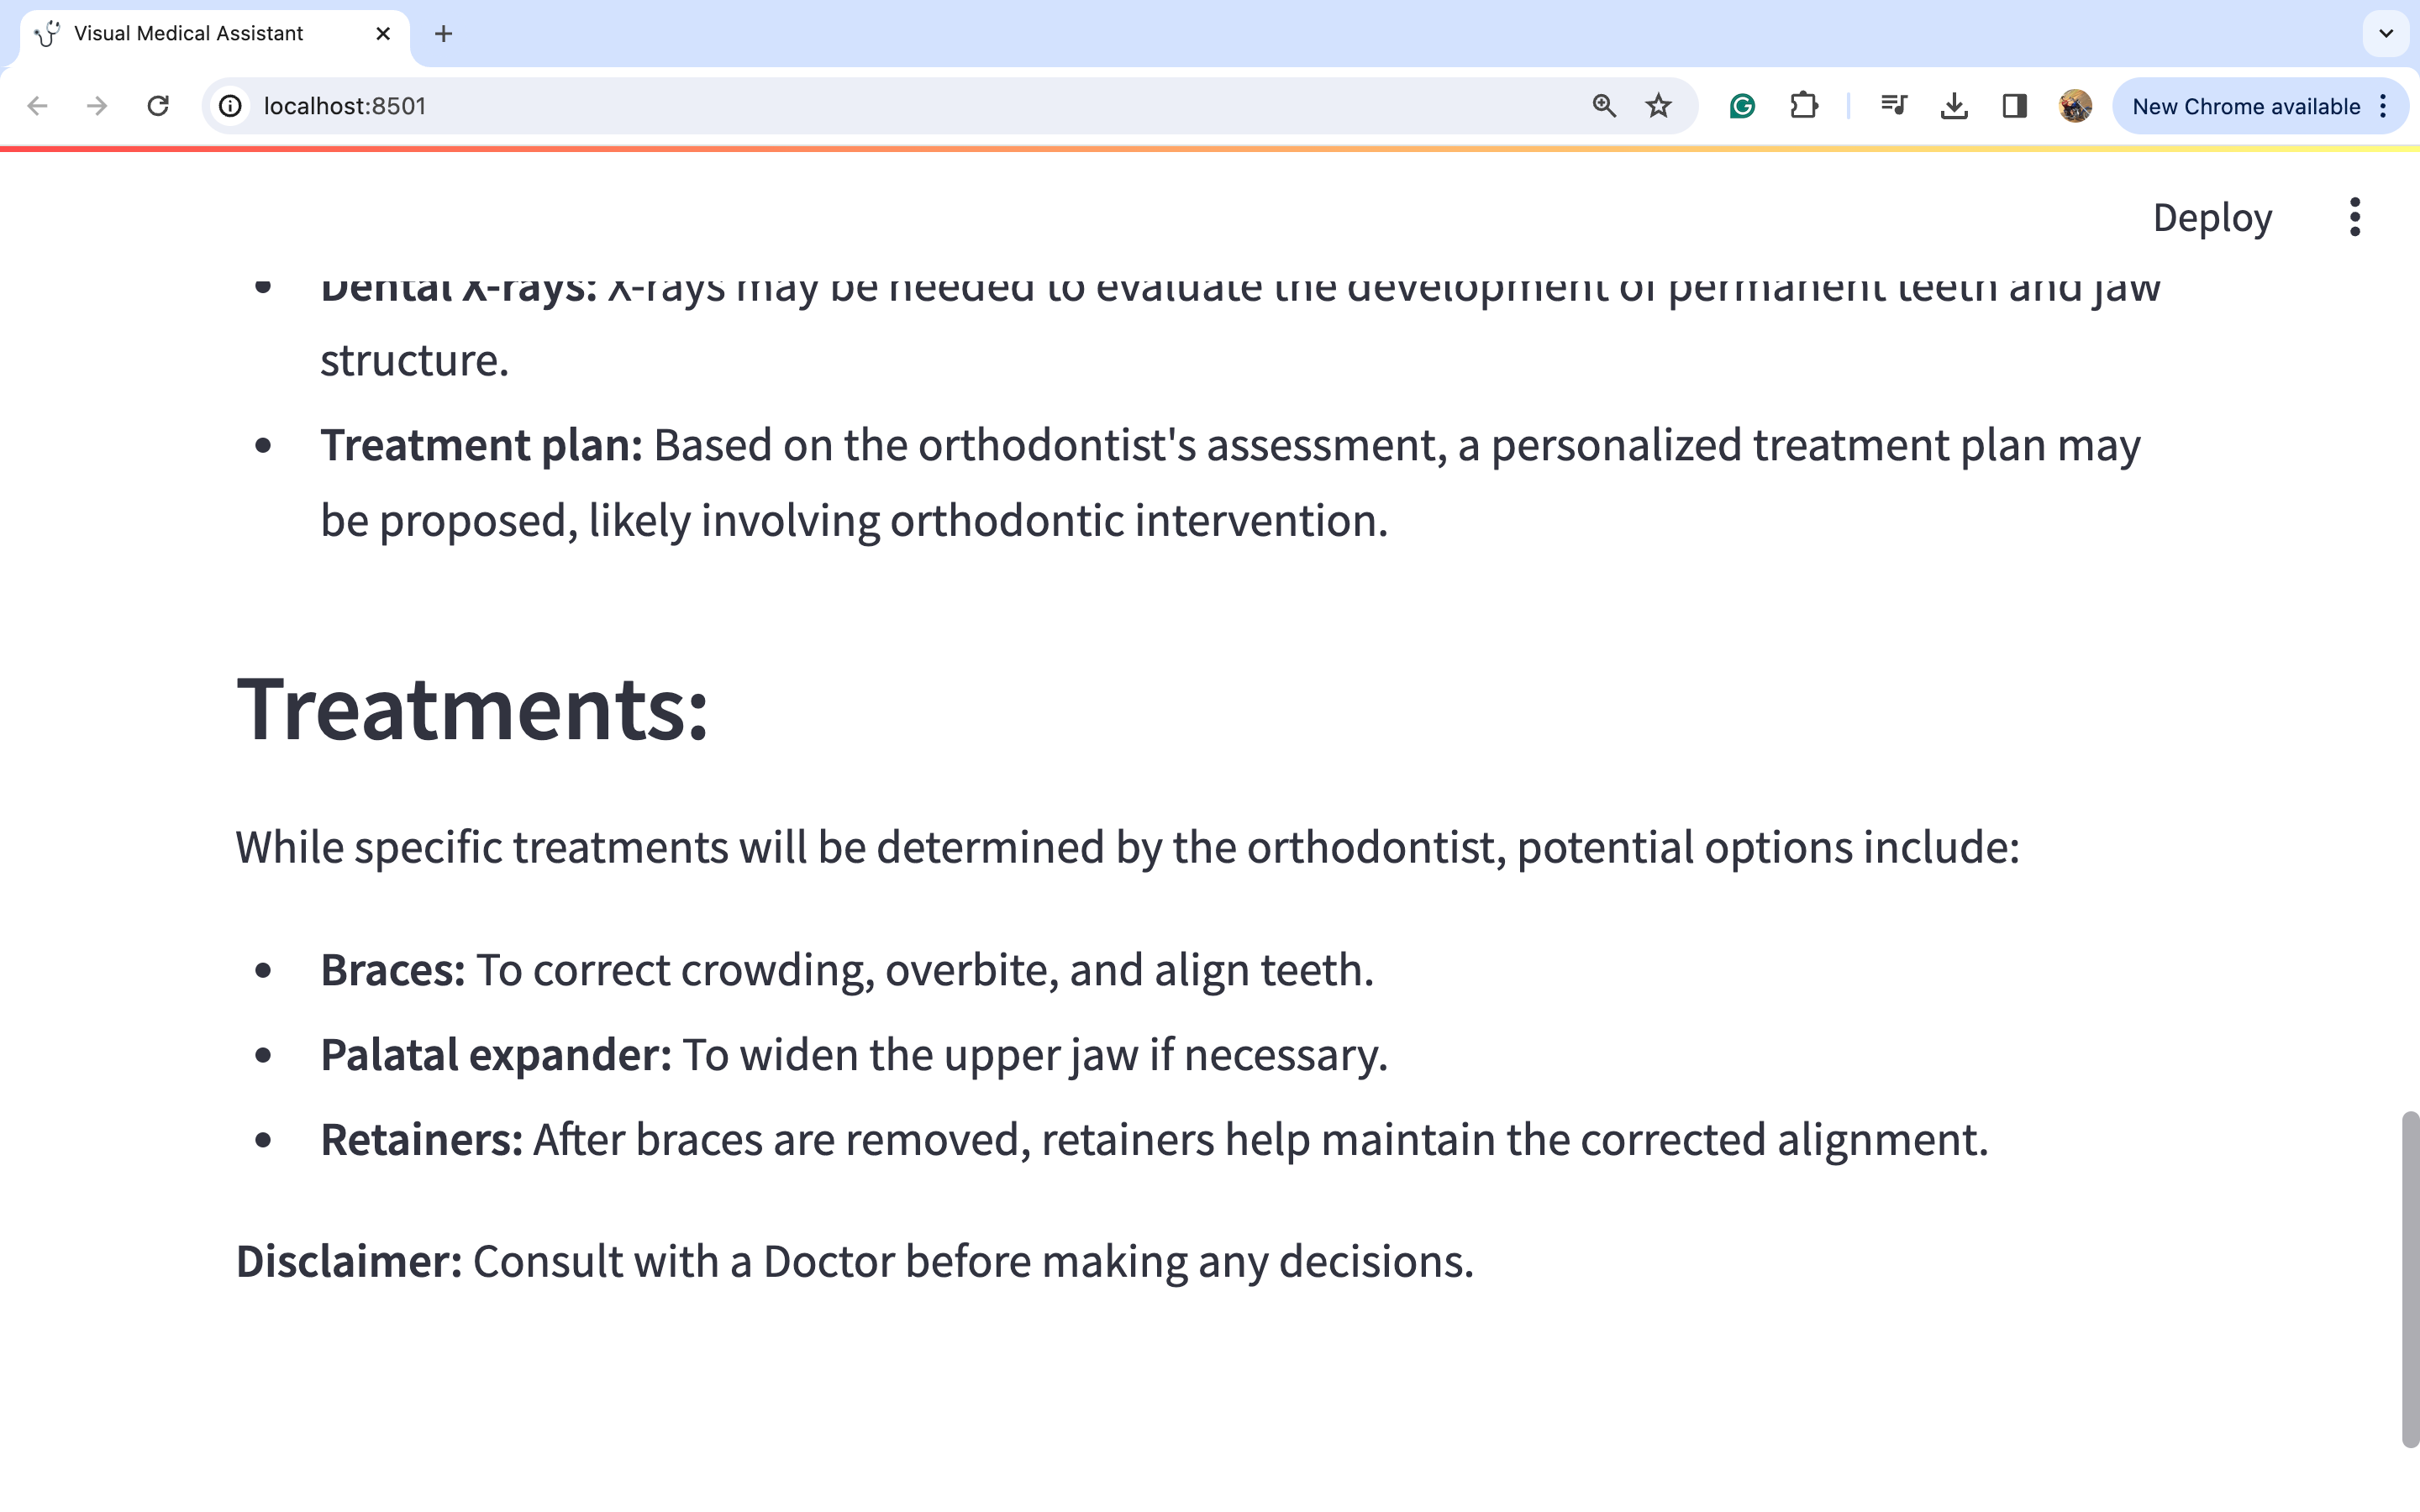

图片2:

通过仔细观察图片,我们可以对潜在的医疗诊断进行深入分析。此外,考虑到这与牙齿问题有关,建议的行动方案是咨询正畸医生并进行一些牙齿X光检查。此外,在这种情况下,佩戴牙套和保持器等多种治疗选择似乎是明智的选择。